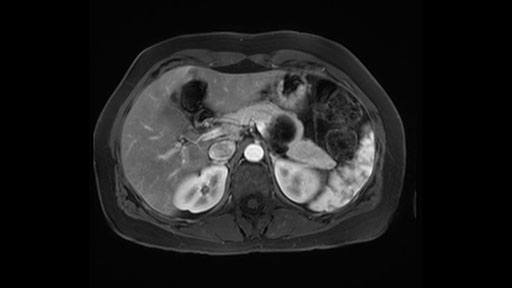

In reviewing this patient’s CT scan, first of all, the lesion is again cystic with a very thin wall. I anticipate that it will be delicate and potentially friable. And therefore the risk of rupture exists and we need to be very careful in how we handle the pancreas and the tumor throughout the procedure.

The lesion itself is quite adjacent to and abuts the splenic vein and therefore we need to anticipate that these two structures will be intimately related and possibly impossible to separate between the two.

The slowing down moments or considerations that I give when I look at the scan and plan my distal pancreatectomy is how far away the tumor is to the portal vein and do I have to formally create a tunnel behind the pancreas on top of the portal vein or do I have to take the pancreas further to the left of the portal vein or the patient’s left of the portal vein. So here I can see that here is the tumor here. I can see that the tumor is a fair way away to the patient’s right and so I will likely not have to take or create the tunnel formally in this procedure. And that speaks a lot to the resection margins. So its important when you’re doing a distal pancreatectomy or any procedure potentially for oncologic reasons to get clearance of the tumor and to take the tumor kind of intact.

The second slowing down moment or consideration I give to a distal pancreatectomy is the anatomy of the portal vein and the splenic artery. And so I look here and the anatomy is pretty straightforward. The splenic vein comes off normally and runs behind the pancreas and I can see the artery superior to that, again coming off in a normal manner from the celiac axis. So those two things, the portal vein and the splenic artery will be taken normally in this procedure.